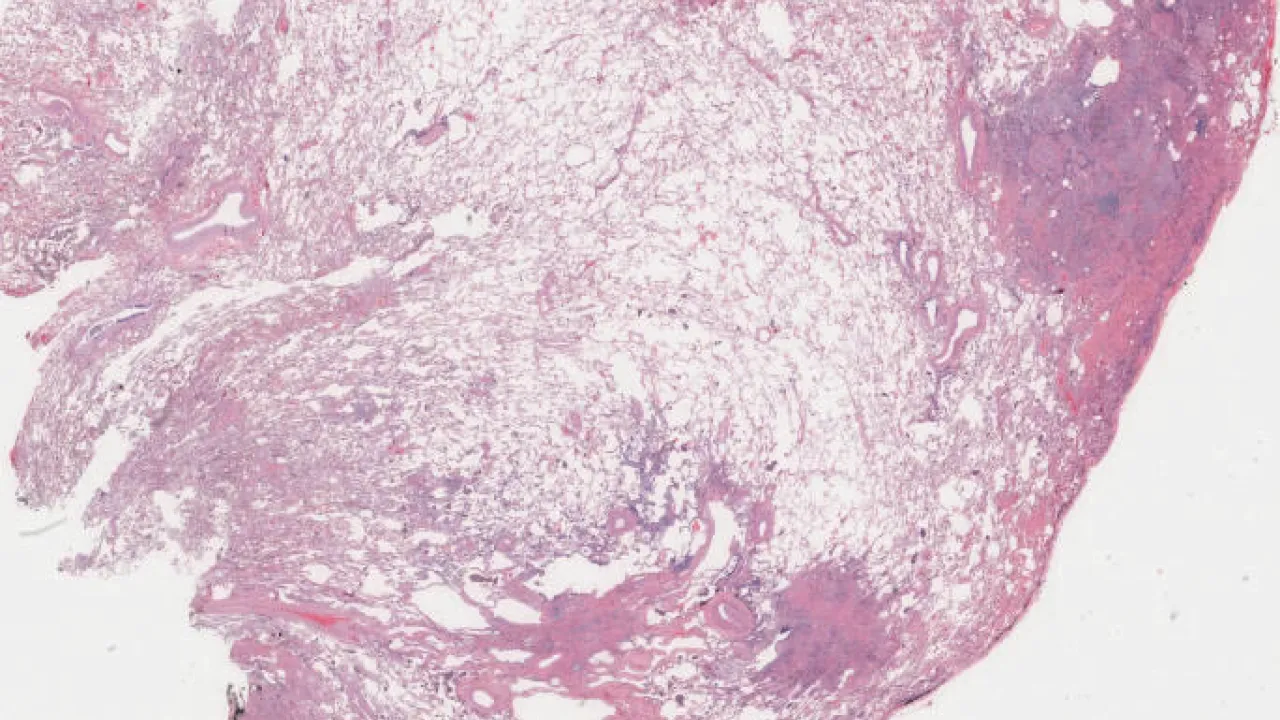

Soft Tissue, Dedifferentiated liposarcoma